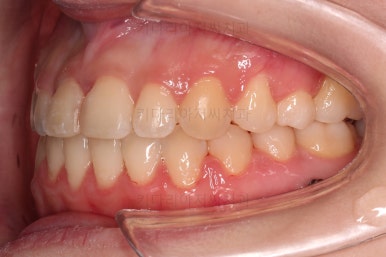

초진 시, 입안의 모습입니다.

아래 중앙선이 윗니의 정중선에 비해 우측으로 많이 쏠려있고요.

전반적으로 아래 치열이 우측으로 가 있어서 특히 송곳니 부분에서의 반대교합이 두드러졌어요.

(아래 송곳니가 위 송곳니보다 밖에 나와있는 상태)

폭이 맞아지고 치아 배열을 조금 시행하니 송곳니 부분에서의 반대교합이 금새 개선된 것을 알 수 있으실거에요.